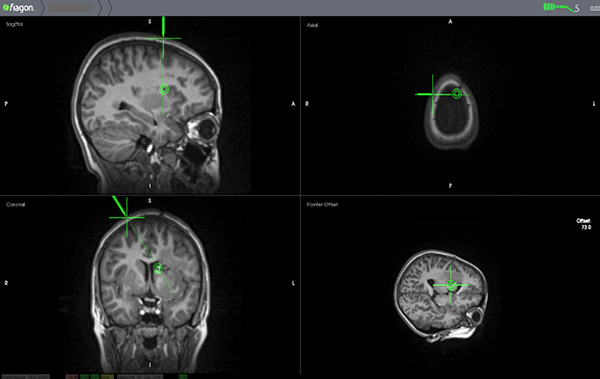

Para el presente caso se incorporaron las imágenes de RMI al equipo de neuronavegación electromagnético provisto de una cánula de aspiración maleable de 3 mm con cursor de navegación “on tip” incorporado (Faigon © origen Alemania). Se trazó la trayectoria marcando como blanco el sitio de aparente irrupción de la sangre en la pared lateral de la prolongación frontal durante el episodio hemorrágico de presentación del Cavernoma (Figura 3).

Figura 3: Planificación de la trayectoria mediante Neuronavegación.